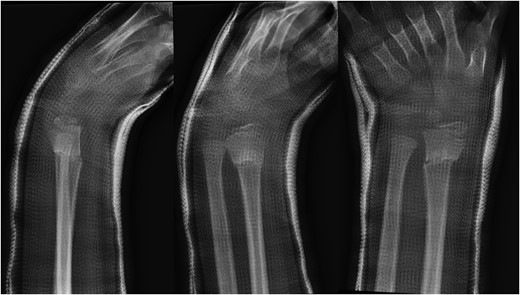

A 10-year-old male was referred to our office after being seen by a pediatric orthopedic surgeon for a distal left forearm mass with block in pronation and supination. The patient's past medical history is significant for a distal radius fracture 2 years prior to his aforementioned office visit. Follow-up radiographs after fracture union at that time showed no evidence of disease (Fig. 1). Radiographs taken at the time of presentation 2 years after fracture healing revealed a 6.5 cm long lesion in the distal syndesmosis arising from the radius. The lesion resulted in pressure erosions upon the distal radius and ulna, causing a slight splaying of the bones (Fig. 2).

AP and lateral radiographs of the left forearm showing 6.5 cm long lesion in the region of the distal syndesmosis between the radius and ulna.